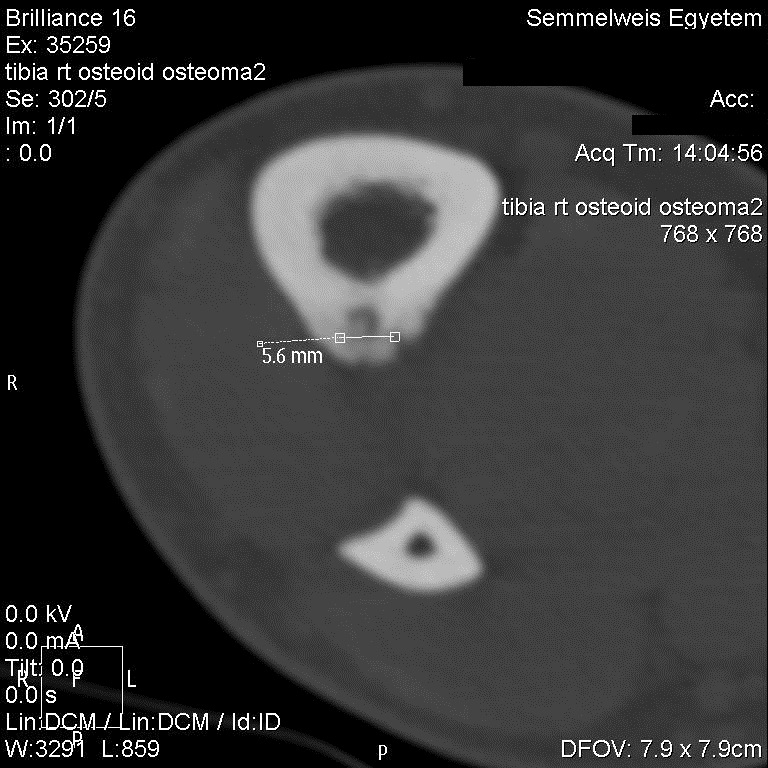

RF ablation is especially useful technique and has a good outcome in the direct treatment of osteoid osteomas (figure 20.) The invasiveness of the method is several folds smaller than orthopedic surgery.

Image

A

B

Figure 20. – RFA treatment of osteoid osteoma in the right tibia (A: CT exam before the treatment, B: RFA)

Patients treated with RFA only require 1-2 days of hospitalization as opposed to the ones undergoing open surgery, who need to stay in the hospital for 7-10 days.